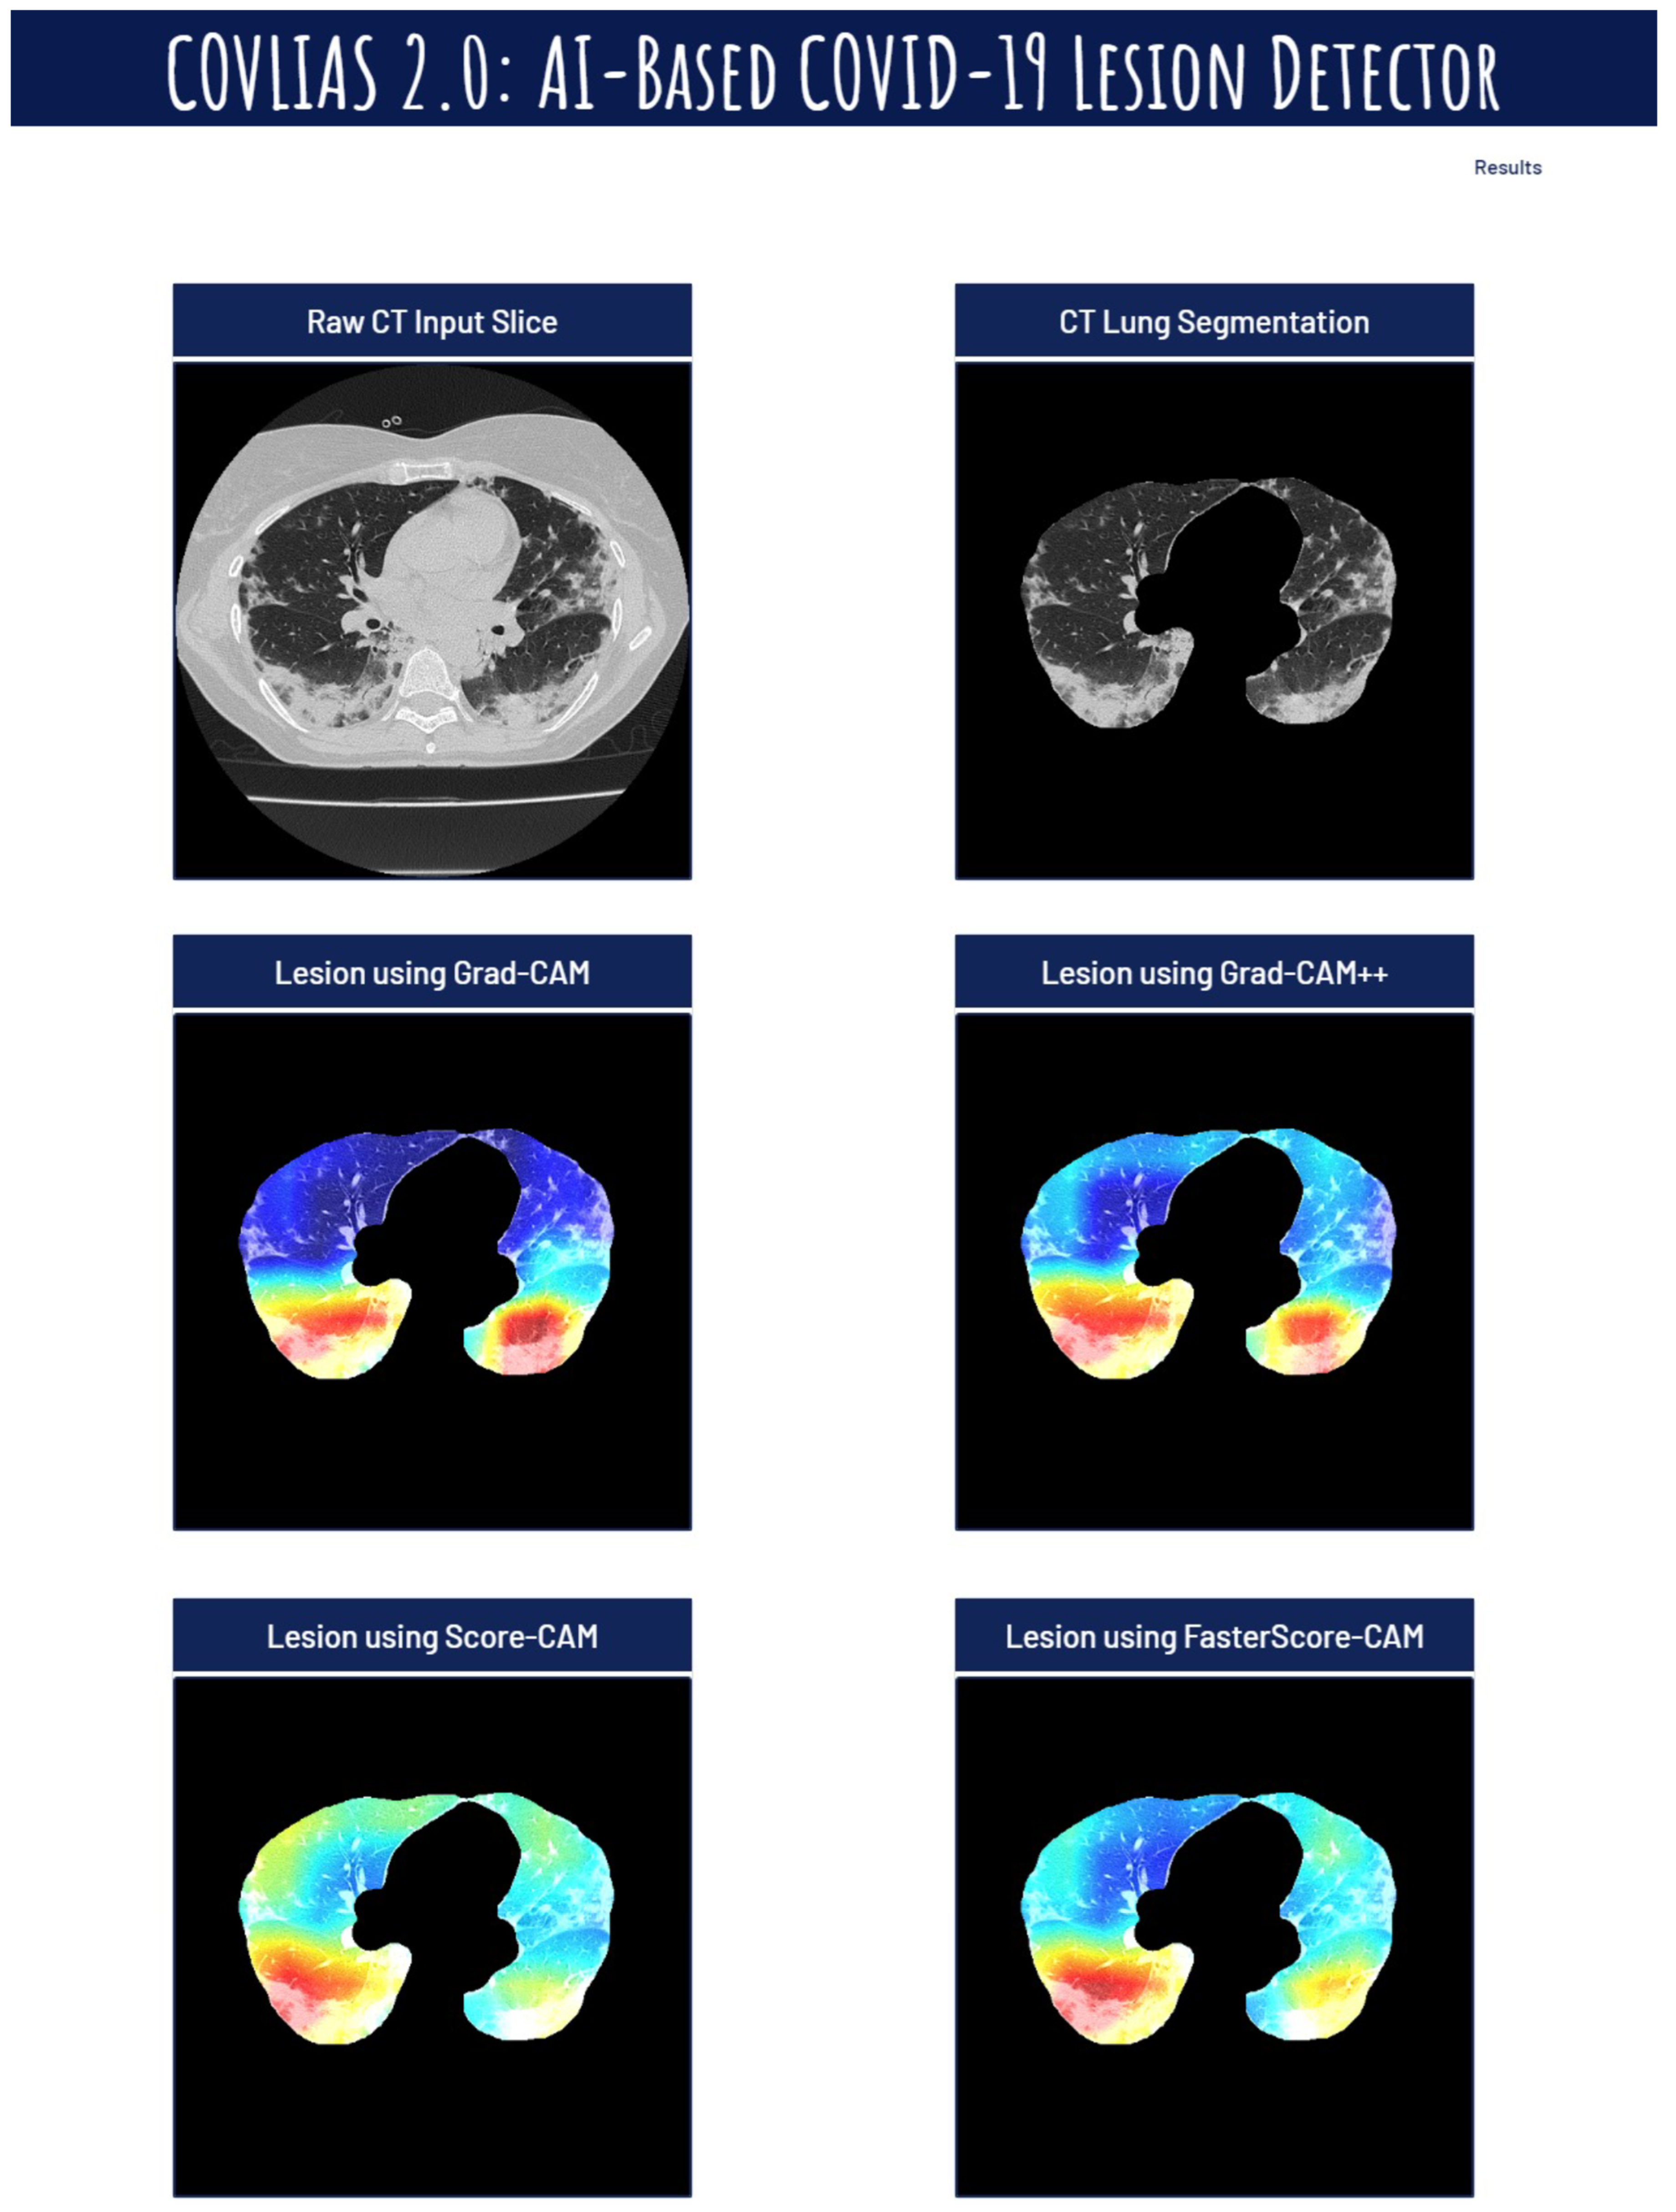

Visual Results Representing Lesion Using the Four CAM Techniques